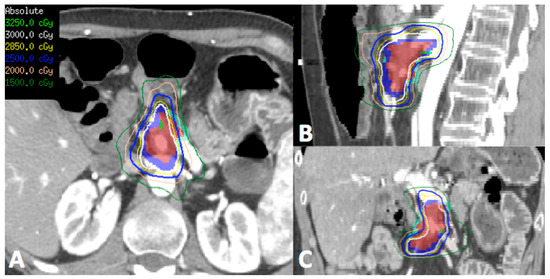

In patients who have had previous radiotherapy, it is imperative to obtain previous treatment plans to assess dose in relation to surrounding normal structures, in particular the duodenum, small bowel and stomach (Figure 1). Reirradiation in this setting could potentially cause significant late effects, depending on the cumulative doses to the normal structures. SBRT is becoming increasingly accepted when patients are considered for reirradiation in the attempt to maximize dose to the tumor whilst limiting the dose to surrounding normal organs thereby reducing the risk of significant late effects.

Figure 1.

Representative transverse (A), sagittal (B) and coronal (C) images of the reirradiation treatment plan using stereotactic body radiotherapy (SBRT) for a patient who had previous 3D conformal radiotherapy to the region 5 years ago to 50.4 Gy in 28 fractions. (Red—gross tumor volume, Dark blue—target for 30 Gy, Light blue—target for 25 Gy due to proximity to surrounding bowel and stomach). Patient tolerated treatment well with Grade 1 nausea and was alive 12 months post-treatment with no significant late toxicity.

SBRT is potentially a feasible and safe option in patients with local recurrence. Table 2 summarizes the studies where SBRT was utilized in the setting of local recurrence with the majority of publications on patients who received previous radiotherapy. As this group of patients is small, the evidence is limited to retrospective studies alone. Nevertheless, from Table 2, SBRT can achieve good local control (1-year freedom from local progression of 62–91%). Although the incidence of grade 3 or higher late toxicity is rare, great care should be taken at treatment planning and delivery with regards to the stomach and bowel dose as gastrointestinal toxicity may cause significant morbidity to this group of patients with limited life expectancy.